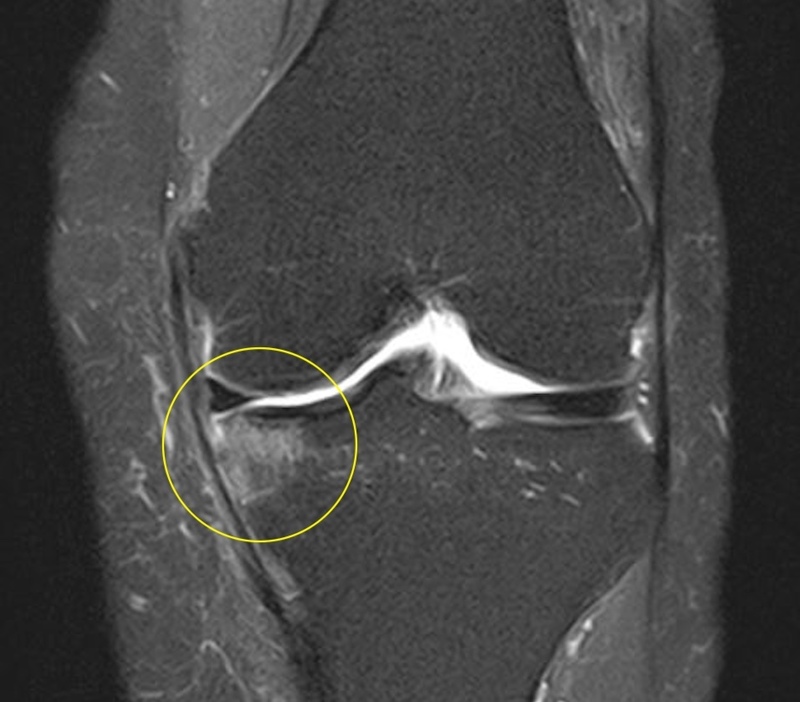

MRI検査

また骨にもダメージがあり骨にも炎症が起きている状態 半月板

骨挫傷

行ったコンビネーション治療

PRP+体外衝撃波治療

膝の関節内にPRP治療を施行

目的:膝の炎症症状の改善と組織修復

膝の骨に対して体外衝撃波治療を施行

目的:骨の炎症症状の改善と組織修復の促進施行後のMRI画像

疼痛消失までの通院回数(その後のリハビリは除く)